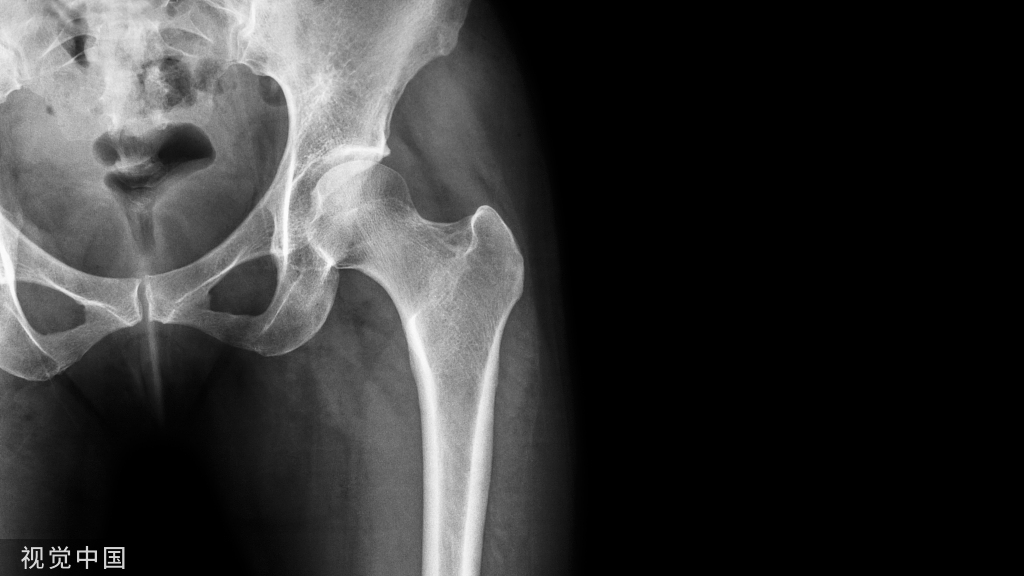

对应的X线表现:

正位